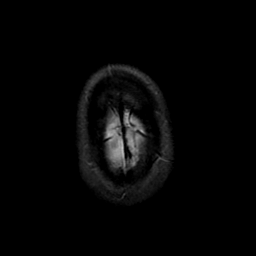

MR Study #23, January 26, 1992 -- Slice #47

[Home][Help][Clinical][Tour 1][Tour 2] Slice 47